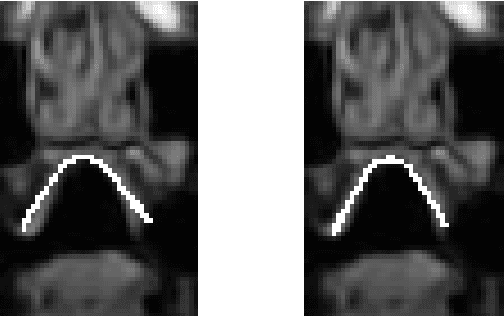

Abstract:We describe a minimally-supervised method for computing a statistical shape space model of the palate surface. The model is created from a corpus of volumetric magnetic resonance imaging (MRI) scans collected from 12 speakers. We extract a 3D mesh of the palate from each speaker, then train the model using principal component analysis (PCA). The palate model is then tested using 3D MRI from another corpus and evaluated using a high-resolution optical scan. We find that the error is low even when only a handful of measured coordinates are available. In both cases, our approach yields promising results. It can be applied to extract the palate shape from MRI data, and could be useful to other analysis modalities, such as electromagnetic articulography (EMA) and ultrasound tongue imaging (UTI).